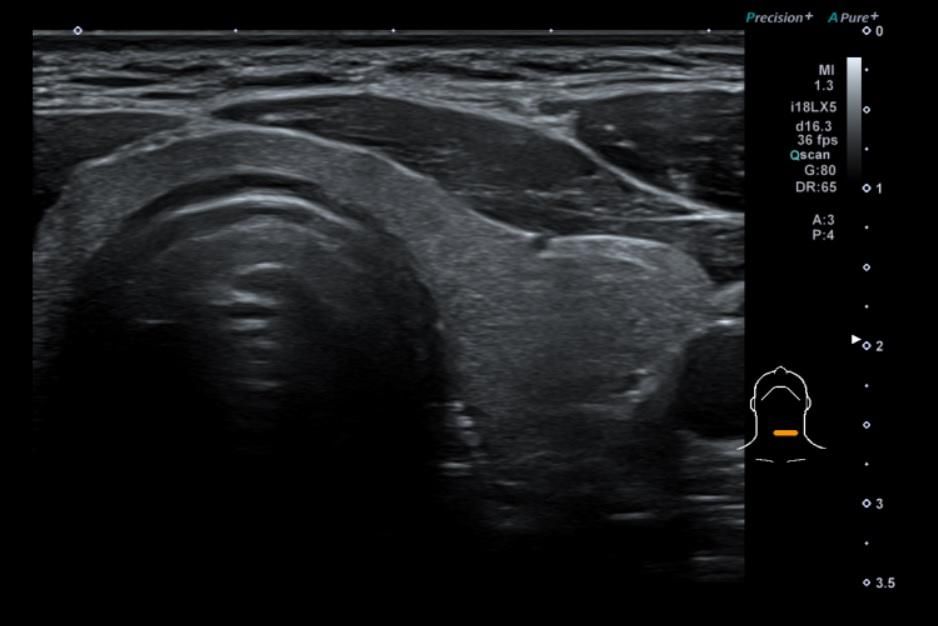

턱뼈안쪽의 침샘 부분과 임파선 부분에 약간의 통증이 있어서, 두경부 초음파 검사를 했습니다.

침샘은 약간 크지만? 문제없다. 라고 하셨고

임파선도 아주 양호 하다고 하셨어요.

갑상선과 경동맥도 함게 부탁드렸는데, 경황이 없어서? 그부분은 대답을 듣질 못하고 왔네요;

실비 청구하면서 혹시나 해서 CD 받아와서 열어봤는데, 일반인 잘 알수는 없어서 문의 드리고자 글 드려봅니다.

1. 판독부탁드립니다.

2. 침샘/임프절/갑상선/경동맥...........4가지다 검사가된건지요